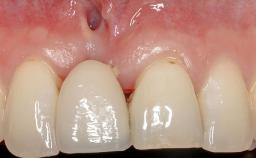

Connective-Tissue Graft to Increase the Width of the Keratinized Mucosa Around an Osseointegrated Implant

Adequate peri-implant soft-tissue thickness is essential not only for esthetic but also for functional reasons. In this case, Vincenzo Iorio Siciliano demonstrates how he achieved increased height and thickness of posterior peri-implant soft tissues to obtain a stable mucosal seal and a width of keratinized tissue favorable to toothbrushing.

The patient, a healthy 38-year-old woman, was referred for increasing the width of the keratinized tissues at the buccal aspect of dental implant 46. The site exhibited a premature-closure screw exposure caused by trauma during chewing, with inadequate keratinized tissue.